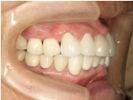

30代女性

事故のため、前歯を2本失いました。

インプラントと矯正治療をしました。

![]() |

| 治療前 | ||

| インプラント後、仮歯を入れました。 | ||

| 矯正設置を着用し、歯列矯正を行いました。 | ||

| 治療後 | ||